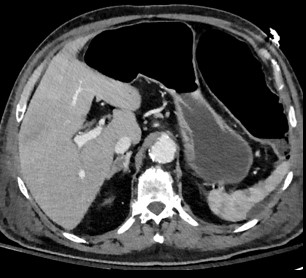

Digestif Vasculaire Staff / Revue de cas Foie Rein Petit bassin Artériel Veineux Pancreas Surrénale

• Choc